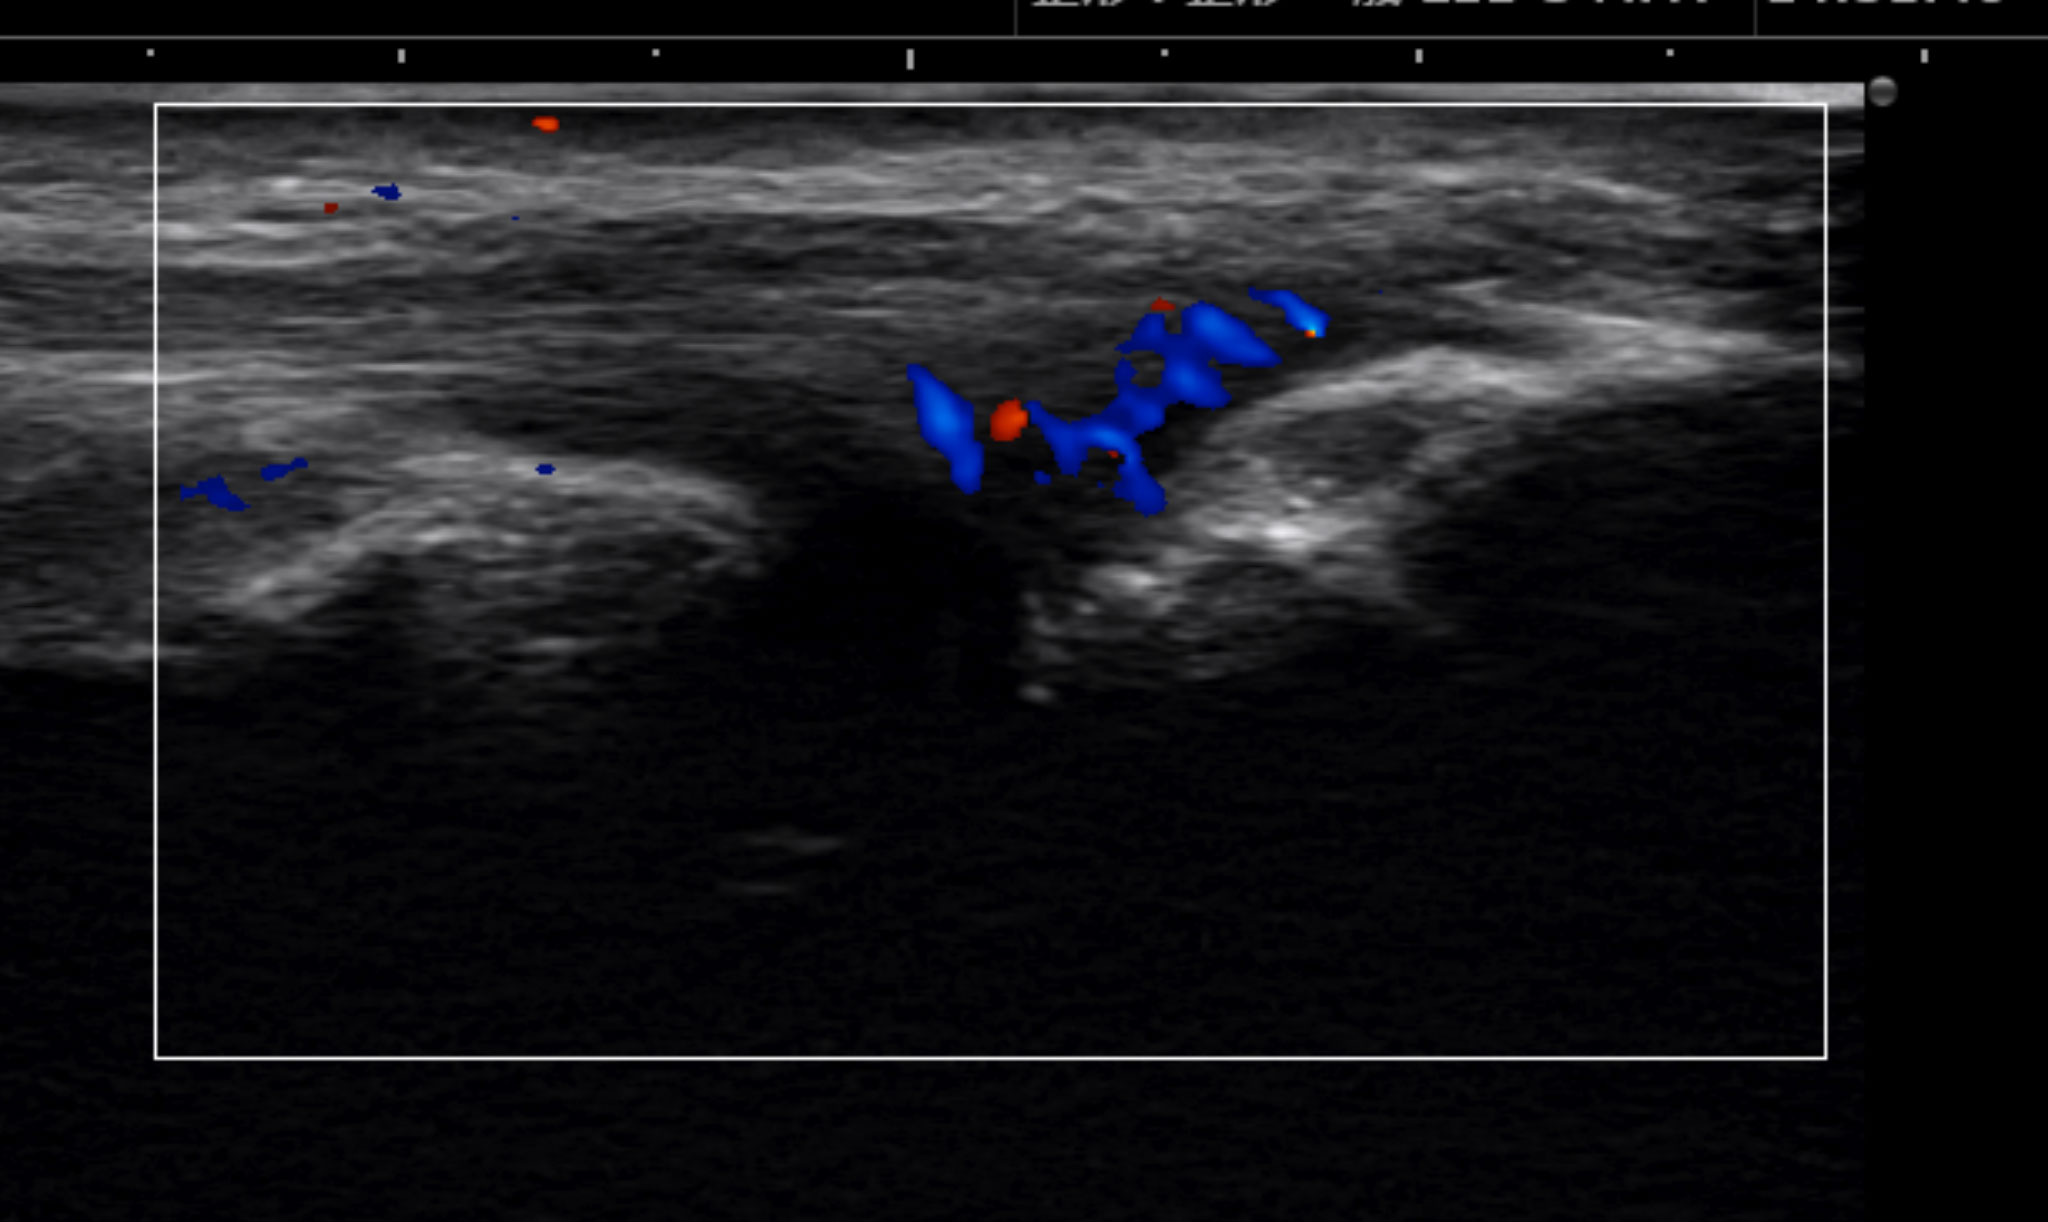

หากสงสัยว่าอาจเป็นโรคอื่นนอกเหนือจากข้อศอกนักกอล์ฟ อาจมีการตรวจเพิ่มเติมเพื่อช่วยแยกโรค โดยการตรวจที่มีประโยชน์มากที่สุดคือ การตรวจเอกซเรย์คลื่นแม่เหล็กไฟฟ้า (MRI) และ การตรวจอัลตราซาวนด์ (อัลตราซาวด์)

ภาพอัลตราซาวนด์: บริเวณสีแดงและสีน้ำเงินแสดงตำแหน่งที่มีอาการปวด